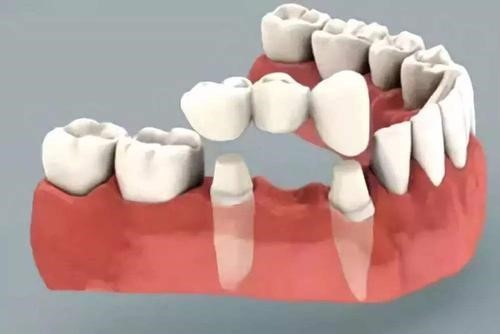

牙齿缺失后的修复方法有三种:

(3)固定义齿:把缺失牙两边的健康牙磨小,变成“桥墩”,然后做牙套套住两边磨小的牙齿,来架住缺失的牙齿。